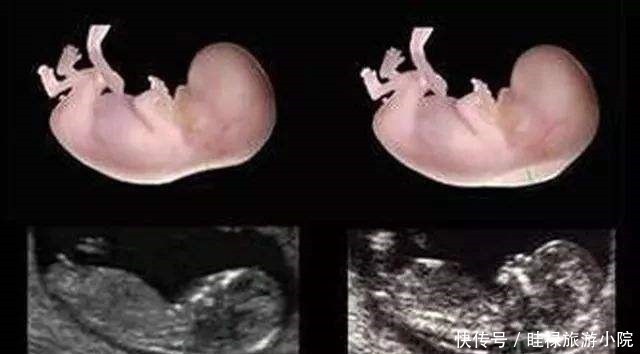

检查时间:怀孕中期,一般在孕24周时检查。现在不少医院大排畸检查,直接做四维B超,会看的更清楚些。排畸检查是孕期最系统的胎儿发育情况的检查,除了检查胎儿的外表可能存在的畸形外,也会检查胎儿内脏的发育情况等。

京妈建议:① 四维排畸检查,一般需要提前预约,因此孕妈要提前咨询医生或护士,提前预约检查的时间;② 四维排畸检查因为看的比较仔细,所以检查时间较长,孕妈要有心理准备,不必担心:检查这么长时间是不是胎儿有问题;③ 孕妈提前做好准备,耐心的配合医生检查,别着急;④ 如果在检查过程中,胎宝宝胎动很少,孕妈可以起来走动走动,或喝点水、吃些甜食来刺激胎宝宝活动;⑤ 如果没能一次检查成功,比如胎儿正好挡住了某些部分,看不清楚,那就可以听从医生建议,安排时间再次检查,但不必慌张;⑥ 避免问医生些不该问的问题,比如关于胎儿性别,我国禁止非医学需要的胎儿性别鉴定,所以孕妈要配合医生,尽量避免问,如果问了医生不回答也是正常的,不要因此对医生生气或作出出格行为。⑦ 在胎儿大排畸检查时,一般会做胎儿超声心动检查,主要是了解胎儿各个心脏瓣膜以及心室、心房的发育情况,排除先天性心脏病的可能,孕妈听从医生的安排和建议就好。